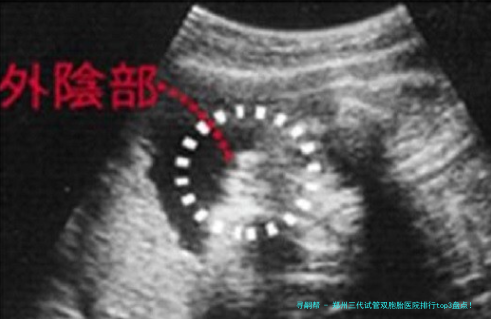

三代试管技术如何科学规划双胎?

很多人好奇:三代试管真正能""孪生儿吗?谜底是:可以科学方案,但不行确保!关键在于胚胎筛选和移植策略。

PGT筛查:通过基因学检测检查筛选优质胚胎,提高着床率

双胚胎移植:一次移植两个优质胚胎,增加双胎概率

胚胎体外培养:将胚胎培育至第五日至六日,检查筛选具发育潜能的胚胎